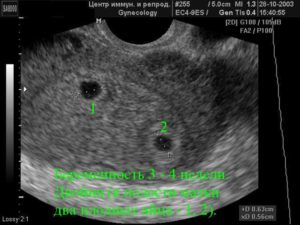

Узи двойни при беременности: фото на ранних сроках в 5-6 недель и позже

Определение двойняшек и близнецов осуществляется таким продуктивным методом исследования, как УЗИ. Этот вид обследования обеспечивает информацией о месте расположения ребенка, имеется ли многоплодная беременность и др.

Как правило, двое эмбрионов четко определяют на УЗИ с самых ранних недель — 5-7. Позже врач способен это определить и без применения ультразвуковой диагностики. Двойняшек можно выявить по такому признаку, как увеличенный размер матки, уже с ранних сроков, а медицинская диагностика с применением ультразвука покажет двух детей только на 1 скрининге — в 10-14 недель.

Двойняшки покажутся на УЗИ уже с 5 недели

В таком случае УЗИ эмбрионов покажет наличие двойни уже на 5 неделе, особенно с применением высокочувствительных датчиков 3д-сканирования. Осмотр дает возможность определить двойняшек только на сроке 9-11 недель.

Следовательно, наличие двойняшек в утробе выявляется посредством ультразвука уже через месяц после зачатия, на снимке они выглядят как 2 образования темного цвета внутри полости матки (см. фото УЗИ-обследования двойни ниже).

Увидеть двойню на УЗИ при беременности можно уже через месяц после зачатия. В этом случае специалист отметит на экране монитора два пятна черного цвета, которые хорошо просматриваются ультразвуком

Считается, что точно увидеть несколько эмбрионов, можно только при помощи УЗИ. На каком сроке определяют многоплодную беременность? Специалист может увидеть данный факт в 5-6 недель. Но, как правило, ее диагностируют во время первого скрининга в 12 недель.